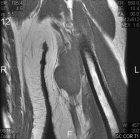

72 year old man left upper arm mass x1 month, accompanied by worsening, constant, dull, minimal pain and tenderness.

No injury

Zoom image: Radiological image Radiological image.